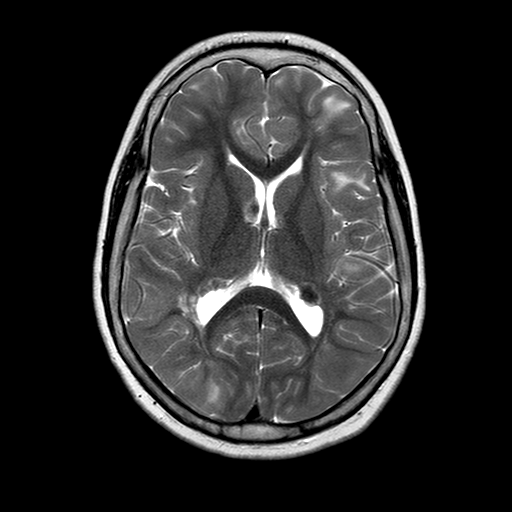

F. � un ragazzo di 12 anni che dall'et� di 5 mesi ha presentato: rabdomiomi cardiaci (evidenziati gi� alla nascita per la presenza di un soffio), 2 formazioni iperecogene in prossimit� del ventricolo laterale sinistro (eco cerebrale), focolai di edema cortico-sottocorticale bilateralmente in sede parietale postero-superiore e multipli noduli subependimali ventricolari con calcificazioni (RMN cerebrale), crisi epilettiche parziali (clonie mano destra e bocca), chiazze ipocromiche al tronco ed arti (pi� di 10). Le crisi, caratterizzate da blocco dello sguardo, scialorrea e disorientamento, sono diventate sempre pi� frequenti, associate a episodi di riso prolungato e ritardo psico-motorio. Viene da subito iniziata terapia antiepilettica con vigabatrin, acido valproico e levetiracetam. A 10 anni comparsa di angiofibromi facciali. Eseguita analisi molecolare che ha evidenziato mutazioni de novo in TSC2. Alla RMN di controllo eseguita a 12 anni: �in entrambe gli emisferi, numerosi tuberi cortico-sottocorticali con aspetti calcifici; 3 noduli subependimali in prossimit� del forame di Monro.� FO: �Amartomi retinici OS�. Il quadro clinico e l'indagine genetica hanno permesso di formalizzare la diagnosi di sclerosi tuberosa (Figura 1 e Figura 2).

Figura 1.